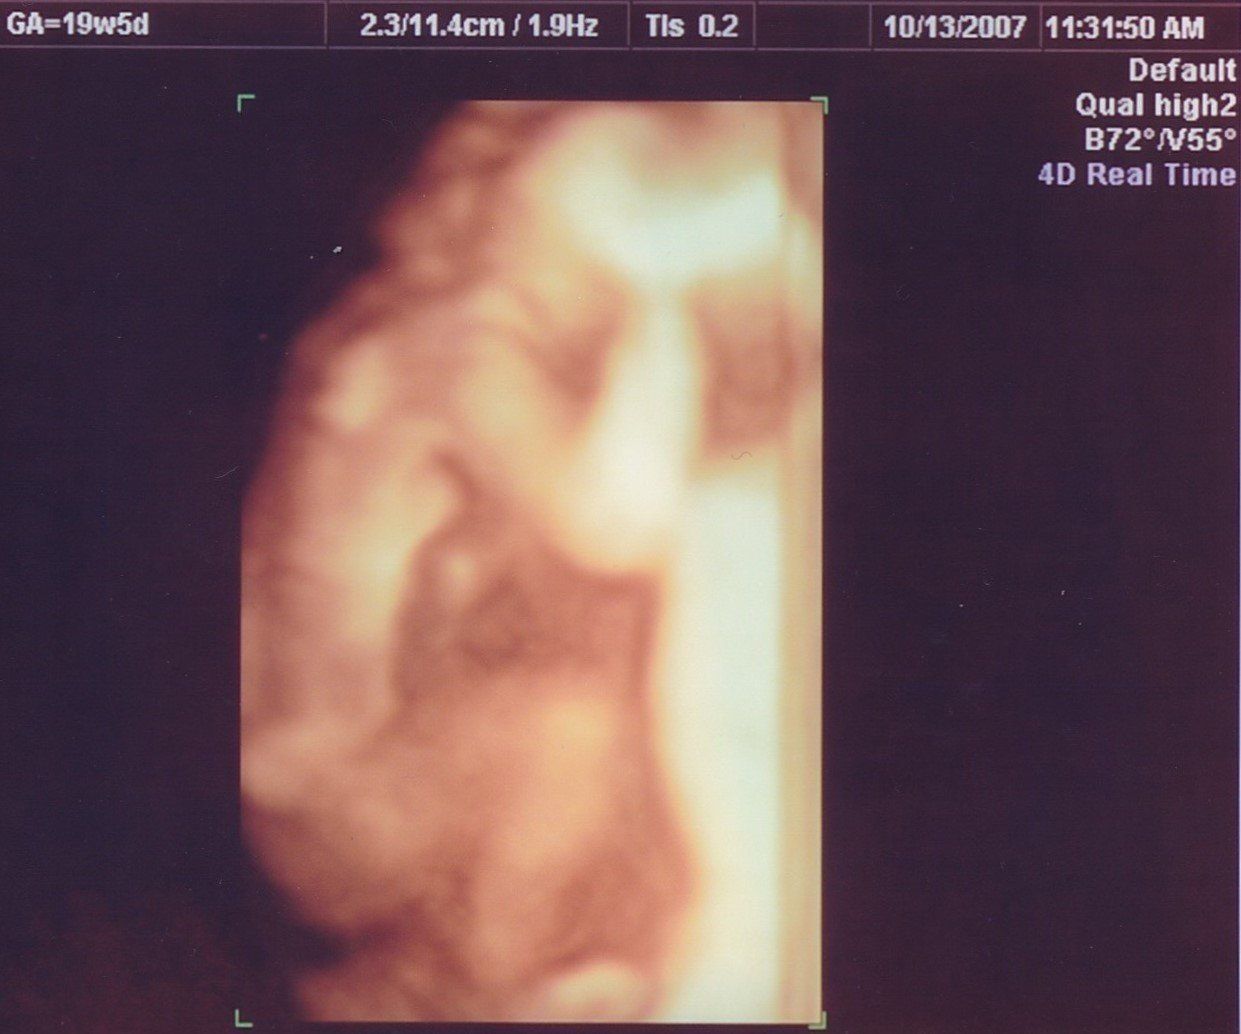

妊娠19週目のエコー写真

安定期に入り、検診のたびに体重や血圧を測るようになりました。前回の検診時から、8~10kgの増加が目安と言われていましたが、妊娠15週から19週の間ですでに1.3kg増。強い食欲と眠気に勝てない毎日に危機感が募り、マタニティーヨガ、マタニティービクスを開始しました。